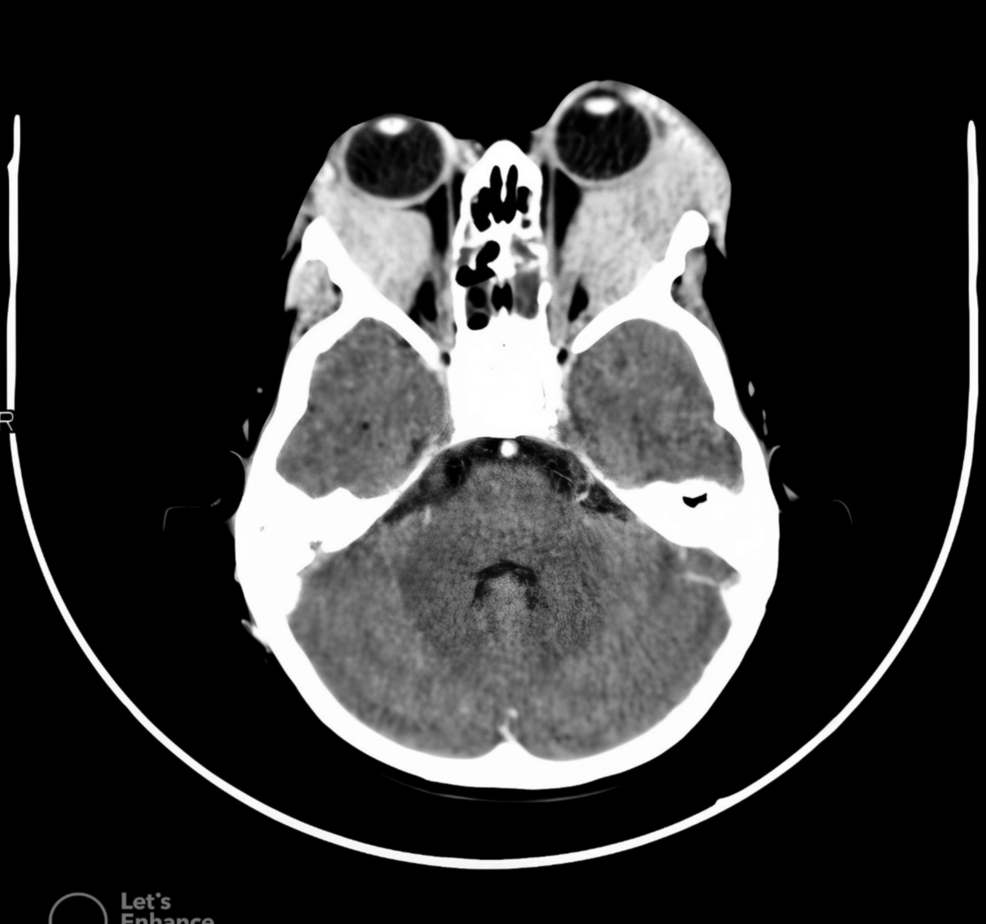

One of the causes of proptosis or swelling behind the eye in children includes vascular anomalies of the orbit such as venouslymphatic malformations (VLM). These lesions, often referred to as lymphangioma can

Pediatric Orbit Tumors and Tumorlike Lesions: Nonosseous Lesions of the Extraocular OrbitRadioGraphics